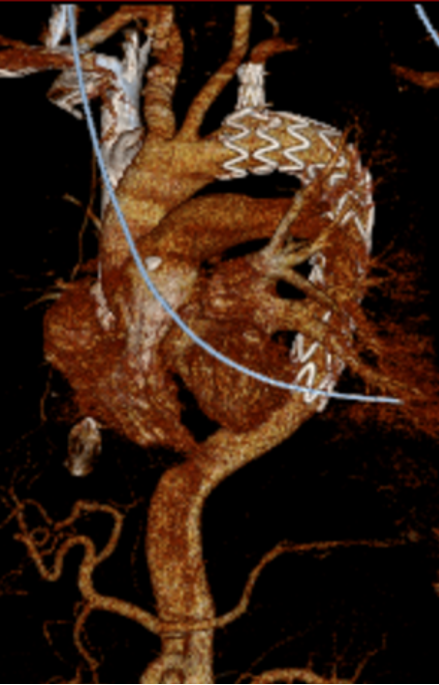

【病例2】主动脉B型夹层,

2016年外院TEVAR术后II型内漏

术后8年随访发现假腔明显扩大,最大直径达96mm,伴胸背疼痛,有手术干预指征。

再干预方案:弹簧圈栓塞分支血管(LSA栓塞),覆膜支架+封堵器+弹簧圈覆盖左肾动脉破口。

修复结果:进入假腔血流明显减少,胸背疼痛症状明显缓解。